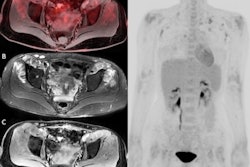

Meanwhile, a January 4 article in the Journal of Nuclear Medicine suggests that F-18 FAPI-04 radiotracer outperforms F-18 FDG in identifying primary tumors, lymph node metastasis, and distant metastases in patients with pancreatic ductal adenocarcinoma (PDAC).